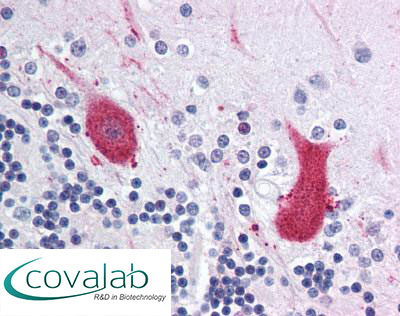

Anti-MARK1 antibody IHC staining of formalin-fixed, paraffin-embedded human cerebellum after heat-induced antigen retrieval.